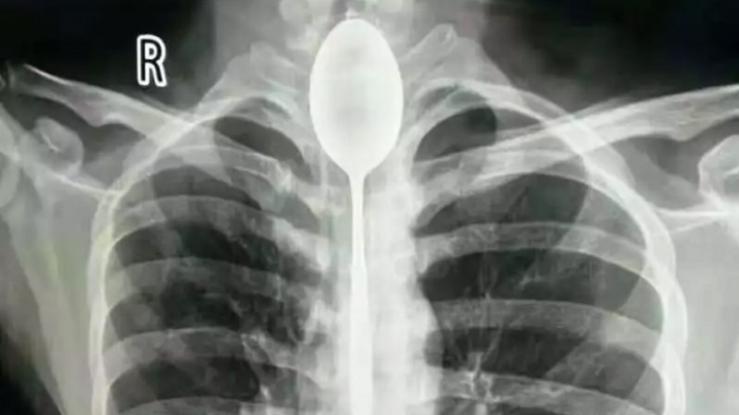

Η κατάσταση του άνδρα είχε φτάσει στο απροχώρητο. Πριν από ένα χρόνο είχε καταπιεί, ένα κουτάλι 20 εκατοστών και δεν είχε πάει στο νοσοκομείο. Το κουτάλι είχε σφηνωθεί στο λαιμό του αλλά εκείνος συνέχιζε να ζει φυσιολογικά. Τον τελευταίο καιρό όμως δυσκολευόταν να αναπνεύσει και έτσι αποφάσισε να επισκεφτεί τους γιατρούς.

Έφτασε στο νοσοκομείο με δυσκολία στην αναπνοή. Ίσα που ανέπνεε, οι γιατροί του έκαναν ακτινογραφία και δεν πίστευαν στα μάτια τους αυτό που έβλεπαν. Το κουτάλι ήταν ακόμη σφηνωμένο στο λαιμό του και εμπόδιζε την αναπνοή του.

Το περιστατικό συνέβη στο Γενικό Νοσοκομείο της Ξιγιάνγκ και ο 21ετών Ζανγκ που είχε καταπιεί το κουτάλι, είπε πως έγινε πριν από ένα χρόνο για να κάνει επίδειξη σε κάτι φίλους του ότι μπορεί να καταπιεί τα πάντα.

Αμέσως μπήκε στο χειρουργείο και οι γιατροί σε μια πολύπλοκη επέμβαση χρειάστηκε 2 ώρες μέχρι να τραβήξουν το κουτάλι έξω.

«Ήταν πολύ τυχερός» είπε ένας εκ των χειρουργών «αντικείμενα στον οισοφάγο ή το στομάχι μπορεί να προκαλέσουν ακόμη και θάνατο».